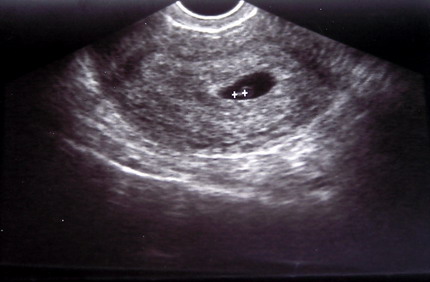

Az UH-s nő azt mondta, vagy nagyon pici még, vagy méhenkívüli. :(

Gyugyi, Te most 5+1 vagy, ugye? Őzinek 5+5 naposan volt 3 mm, lehet, hogy tényleg nagyon pici... jajj, nekem is ezt fogják mondani... de akkor miért uh-znak ilyen korán, valakinek látszik és valakinek nem? Dehát az sem látszik, ha valakinek a méhe meg van nagyobbodva? Nem értek hozzá...

Nagyon sajna, de ne félj, rendben lesz minden. Csak azt tudom neked is írni, mint Vionak, 6. hét körül látszik inkább, előtte csak üres szikhólyag van!!! Erre az egy hétre erősen szorítunk neked, gondolom nem könnyű kivárni. A doki is mondta, hogy nyugi, (mondjuk neki tudnia kellett volna, hogy uh-nak még korai). Biztos nagyon szégyenlős :) !